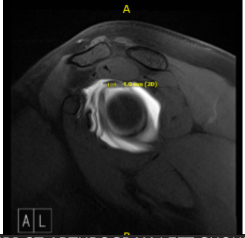

After a week patient returned with MRI result and showed that cervical spine showed significant result of straightening of the normal cervical lordosis, consistent with an element of muscle spasm and shoulder MRI showed tear of the superior glenoid labrum extending into the anchor the long head the biceps tendon.

MRI-3T Arthrogram Left Shoulder